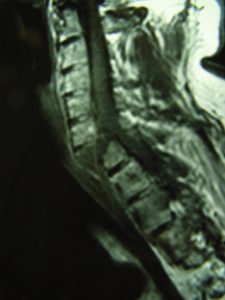

Εικόνα 2 (α,β,γ,δ,ε) Προεγχειρητική Μαγνητική Τομογραφία Α.Μ.Σ.Σ. – Ακολουθία Τ2 και Τ1 Οβελιαία τομή (Sagittal) λίγες ώρες μετά το ατύχημα. Η βλάβη ξεκινά από οπίσθια συνδεσμο-οστικά στοιχεία στο επίπεδο Α6-Α7 και περνά προσθίως μέσα από τον Μεσοσπονδύλιο Δίσκο και την πρόσθια κολόνα του 7ου αυχενικού σπονδύλου. Παρατηρείται μετατραυματικό οίδημα του νωτιαίου μυελού στο σύστοιχο επίπεδο.